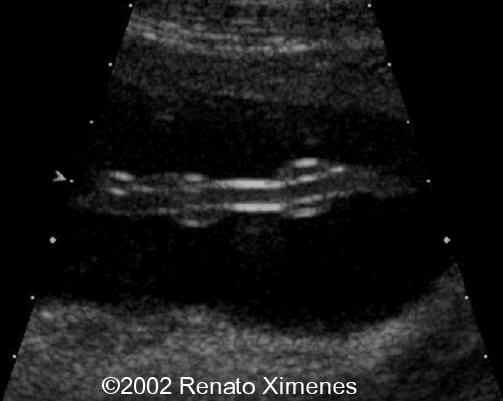

The cord is thin and poorly coiled, a sign associated with decrease fetal motion:

case0072-6